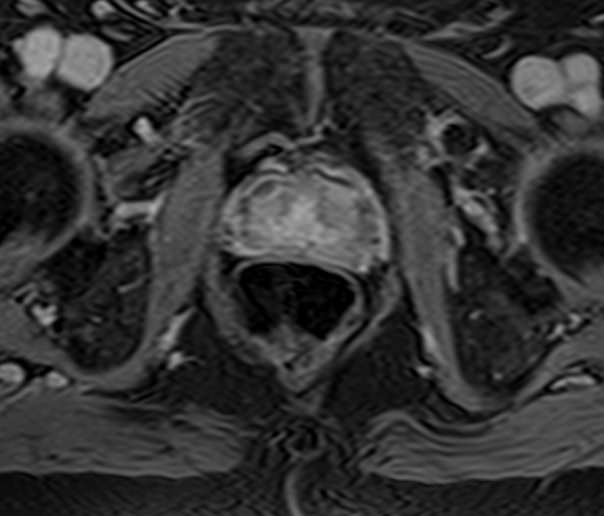

Простата расположена в труднодоступной для диагностики анатомической области, однако метод магнитно-резонансной томографии позволяет детально изучить структуру органа и окружающих ее тканей, включая семенные пузырьки (секреторные органы, вырабатывающие жидкую часть семенной жидкости) и семявыносящие протоки.

При подозрении на опухолевый процесс в предстательной железе в обязательном порядке проводится контрастное усиление. Это подразумевает внутривенное введение контраста, созданного на основе соединений металла гадолиния. Степень и характер накопления контрастного препарата в органах и тканях позволяет различать патологические процессы, в том числе диагностировать опухоли на ранних стадиях, что повышает шансы на успешное лечение.

В клинике «Доступная медицина» диагностика заболеваний предстательной железы выполняется при помощи современного высокопольного магнитно-резонансного томографа экспертного уровня TOSHIBA VANTAGE TITAN 1,5 Тесла. Аппарат производит сканирование в виде послойных тончайших срезов с шагом от 1 мм и преобразует их при помощи инновационных компьютерных программ в изображения трехмерного формата. Методика позволяет получить максимально полную картину о состоянии структуры простаты и окружающих тканей и поставить точный диагноз.